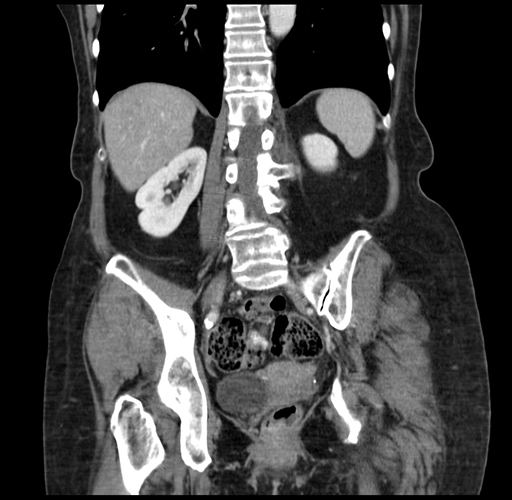

Coronal Venous

Considering a standard right hepatectomy procedure, what step(s) of the operation would you do differently in this case?